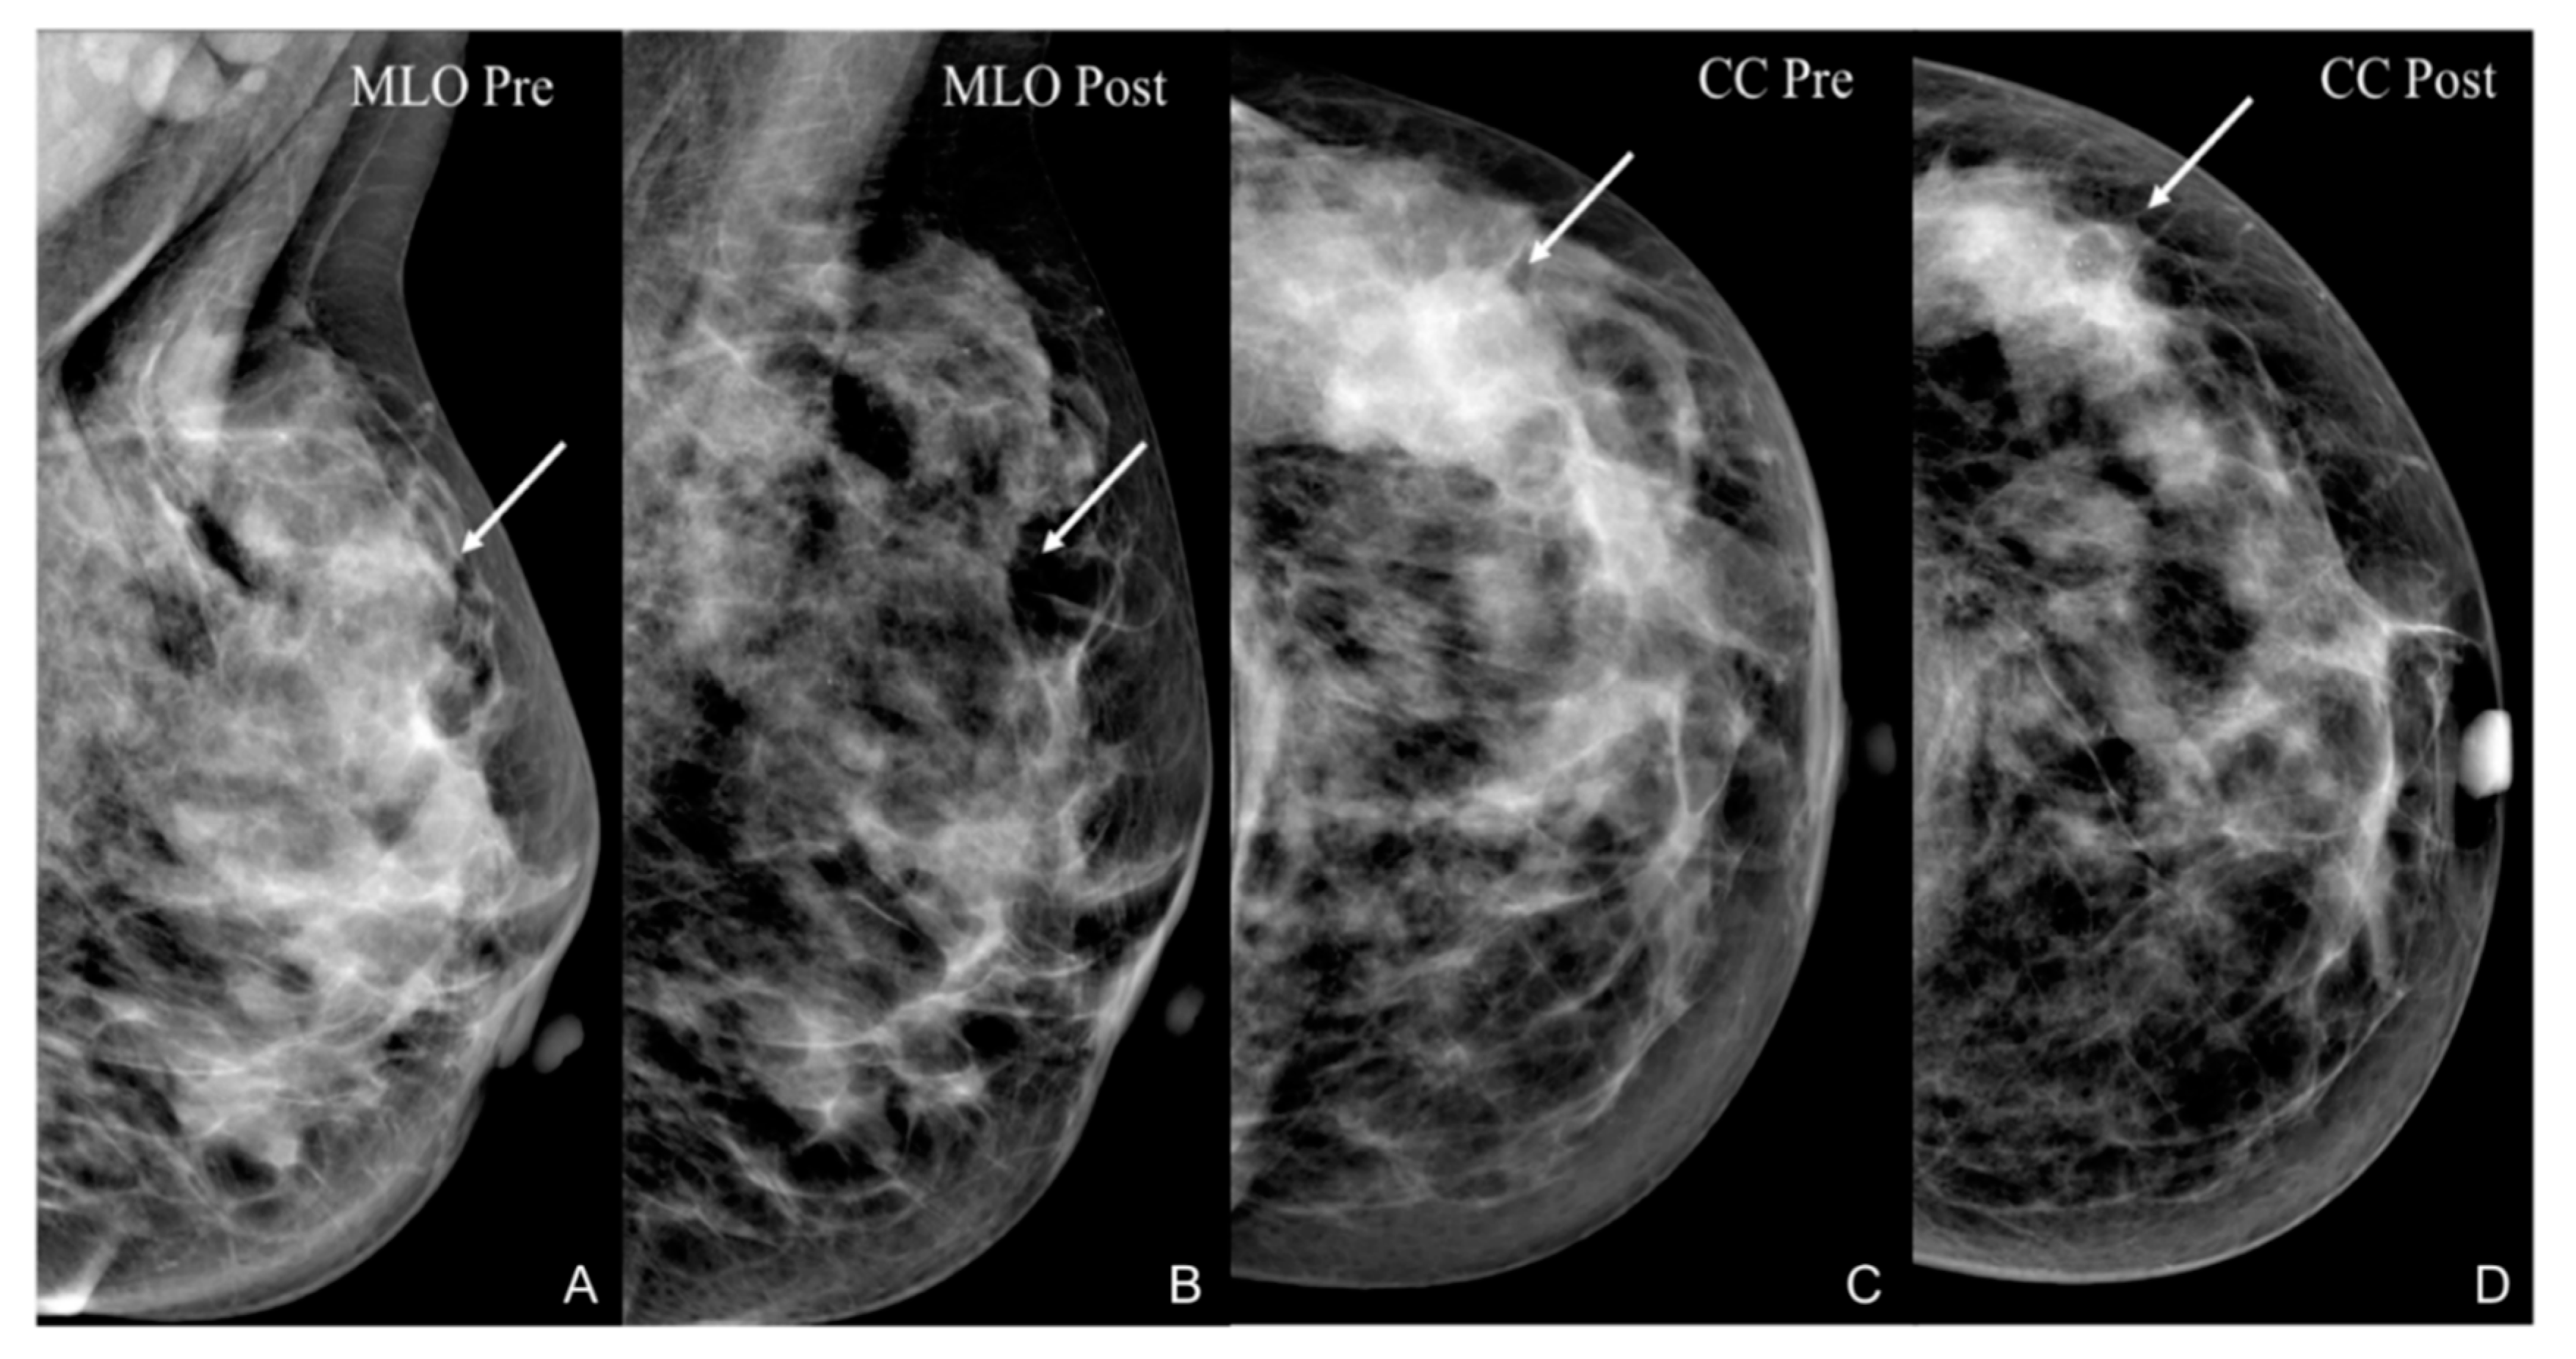

- Park, J.; Chae, E.Y.; Cha, J.H.; Shin, H.J.; Choi, W.J.; Choi, Y.-W.; Kim, H.H. Comparison of mammography, digital breast tomosynthesis, automated breast ultrasound, magnetic resonance imaging in evaluation of residual tumor after neoadjuvant chemotherapy. Eur. J. Radiol. 2018, 108, 261–268. [Google Scholar] [CrossRef]

- Dialani, V.; Chadashvili, T.; Slanetz, P.J. Role of Imaging in Neoadjuvant Therapy for Breast Cancer. Ann. Surg. Oncol. 2015, 22, 1416–1424. [Google Scholar] [CrossRef] [PubMed]

- Rauch, G.M.; Adrada, B.E.; Kuerer, H.M.; Van La Parra, R.F.D.; Leung, J.W.T.; Yang, W.T. Multimodality Imaging for Evaluating Response to Neoadjuvant Chemotherapy in Breast Cancer. Am. J. Roentgenol. 2017, 208, 290–299. [Google Scholar] [CrossRef]